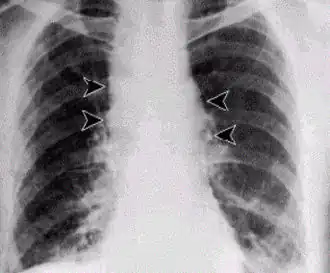

Forma sistémica del carbunco: nótese el ensanchamiento del mediastino. | ||

- En la forma inhalatoria del proceso los síntomas se desarrollan rápidamente y no son específicos. Al principio se produce fiebre con toses no productivas, seguidas de dificultad respiratoria grave, con estridor, cianosis y septicemia fatal. Los rayos X muestran una expansión típica del mediastino, la muerte ocurre en un corto período en casi todos los casos.[6]